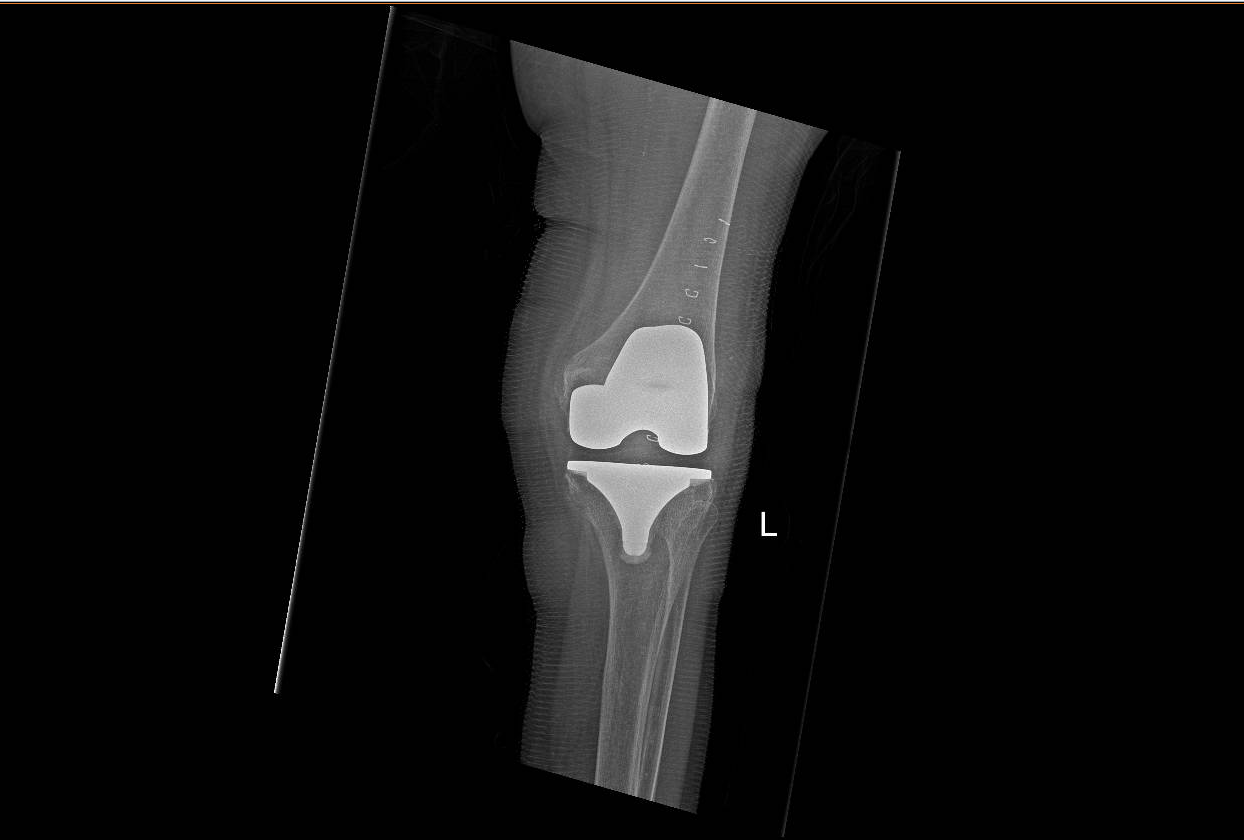

2.png

Hình X-quang khớp gối của người bệnh sau phẫu thuật

Sau đó, các bác sĩ thực hiện gây mê toàn thân liều thấp để nội soi ngược dòng lấy sỏi đường mật cho người bệnh. Đây là một thủ thuật ít xâm lấn, giúp người bệnh hồi phục nhanh, tránh các biến chứng nguy hiểm. Sau khi thực hiện thủ thuật lấy sỏi đường mật thành công, gần 1 tuần sau, người bệnh tiếp tục được thực hiện phẫu thuật thay khớp gối trong tình trạng sức khỏe ổn định.